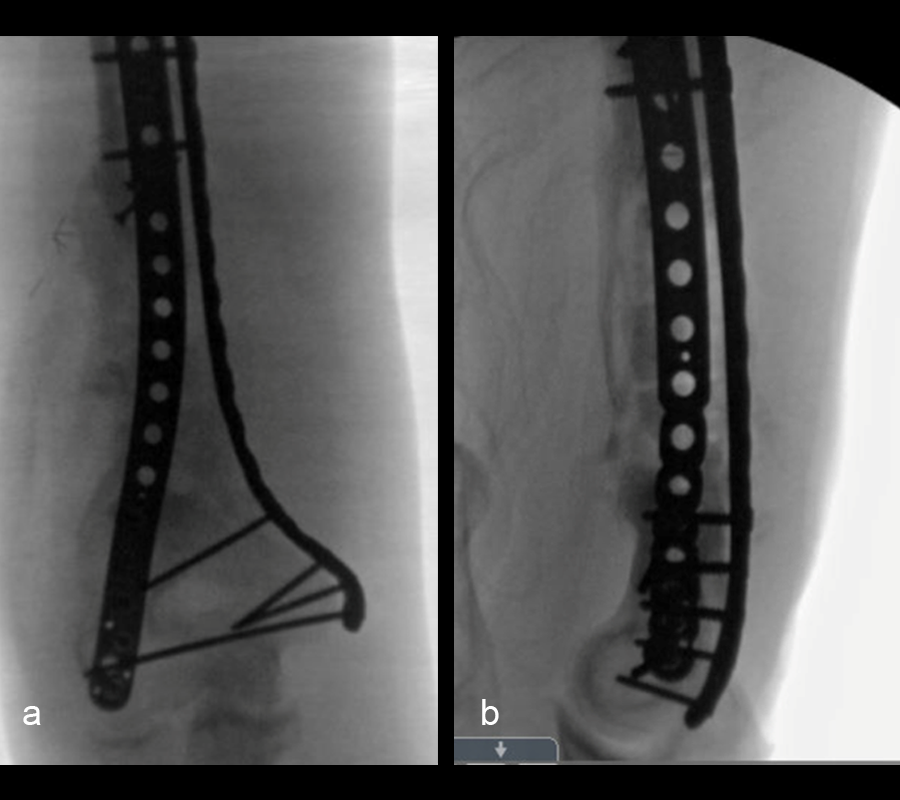

The second stage of surgery took place in October 2022. The cage was inserted (Figs 20-22) and filled with ~20cc autograft obtained by RIA of the femur, 30cc allograft and 3cc BMAC.

Healing progressed well over the following 9 months (Fig 23 - 27). The patient’s pain was well controlled in the early postoperative phase, and he was weaned off the prescribed narcotics after four weeks. He remained smoke free for the first four weeks and then admitted to re-starting his vaping. His elbow ROM improved significantly to 20-125 and good supination/pronation.